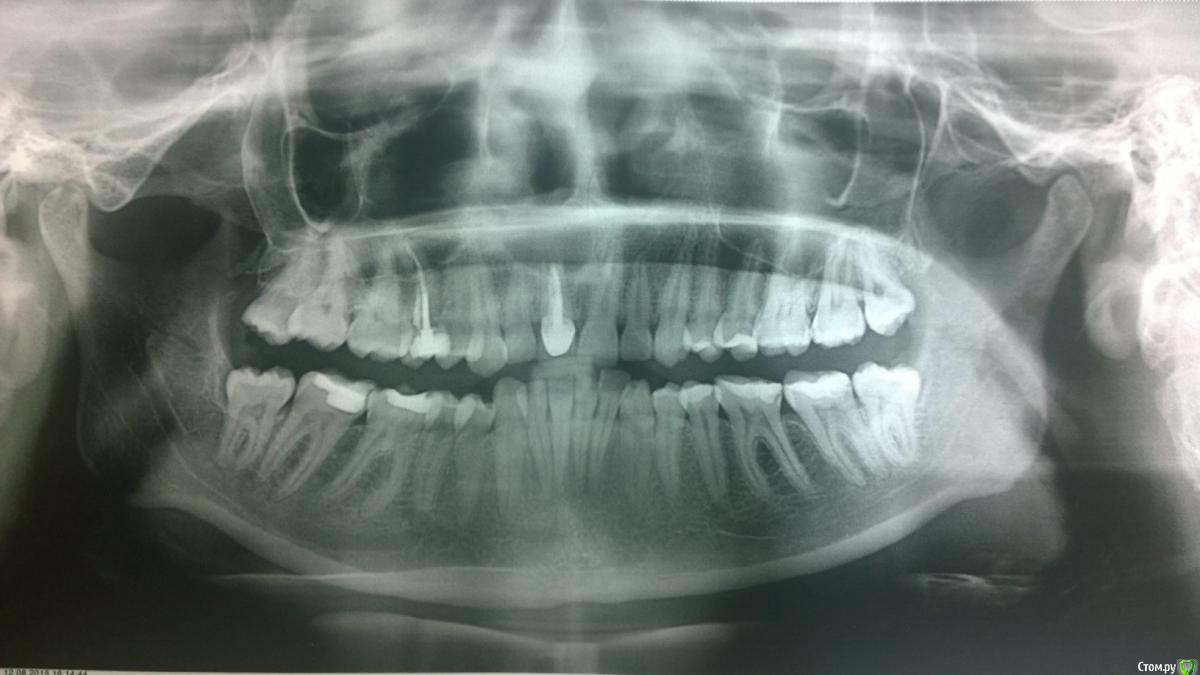

Anet04 Опубликовано 12 августа, 2015 Поделиться Опубликовано 12 августа, 2015 Здравствуйте.Все пыталась сформулировать конкретный вопрос, но проблема в том, что его нет.Есть один большой знак вопроса.Мне сейчас 30 лет и назрела(причем очень давно) операция на переднем зубе.В 7 лет у меня была травма, в результате которой был выбит зуб, с последующими проблемами.Флюс, наращивание, затем коронка.Кисту я сама лично заметила лет в 15, показала врачу, но она предпочла ничего не делать на тот момент.Сейчас к какому хирургу не приду, все на радостях хотят тут же резать, но никто не поясняет схему лечения.Сегодня очередной раз встретилась с хирургом. Он предложил схему лечения.Сказал, что необходимо сделать КТ. Без него не ясно задета ли стенка носа(как я поняла, простите мне мой французский) Не представляю в какую сумму выльется имплант и вообще, если честно плохо понимаю ситуацию. Насколько серьезно промедление с операцией? Мне бы не хотелось трогать соседние зубы. http://s017.radikal.ru/i400/1508/0f/d807958f0155.jpg Ссылка на комментарий

Anet04 Опубликовано 20 августа, 2015 Автор Поделиться Опубликовано 20 августа, 2015 Сделала КТ. Все на диске. Файлов куча, не понимаю, что нужно выложить, поэтому для начала скришот 3D http://s010.radikal.ru/i312/1508/e1/d56d5fa4e845.jpg http://i003.radikal.ru/1508/30/5663df927785.jpg http://s018.radikal.ru/i511/1508/8d/d6212816d709.jpg Ссылка на комментарий

Anet04 Опубликовано 20 августа, 2015 Автор Поделиться Опубликовано 20 августа, 2015 Направляют в челюстно лицевую хирургию, еще не общалась с врачами. Не знаю как все это будет выглядеть. Сколько зубов надо удалять, чем закрывать эту дыру, возможно ли нарастить костную ткань и в дальнейшем сделать импланты? Не хочу просто мосты. Очень боюсь того, что в челюстно лицевой сделают операцию не так, как это надо будет стоматологу в дальнейшем. Хотелось бы максимального сохранения тканей и зубов. Ссылка на комментарий

Anet04 Опубликовано 20 августа, 2015 Автор Поделиться Опубликовано 20 августа, 2015 Я не врач, но насколько я могу судить по снимкам КТ, оголились корни соседнего одного зуба, но пока вроде целые. Опять же - я не врач, если подскажите выложу то, что необходимо. Ссылка на комментарий